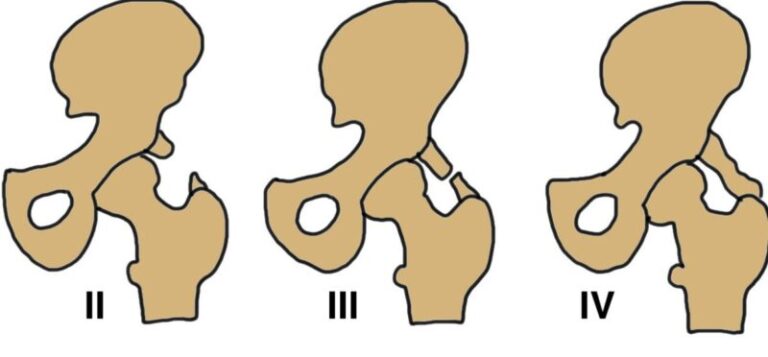

Rothman và Marvel đã chia thoát vị đĩa đệm ra sau thành 3 loại:

- Loại thoát vị trung tâm (central) chủ yếu chèn ép tủy sống gây bệnh lý tủy.

- Loại thoát vị cạnh trung tâm (sau-bên, posterial-lateral) chèn ép cả tủy và rễ thần kinh gây ra bệnh lý tủy rễ.

- Loại thoát vị cạnh bên (xa bên, far-lateral) còn gọi là thoát vị lỗ ghép chủ yếu chèn ép rễ thần kinh gây ra bệnh lý rễ.

HÌnh 3: Phân loại thoát vị đĩa đệm theo liên quan với rễ thần kinh và ống sống. (A) thoát vị trung tâm, (B) thoát vị cạnh trung tâm, và (C) thoát vị xa bên

Cách phân loại này có ý nghĩa rất lớn trong lâm sàng.